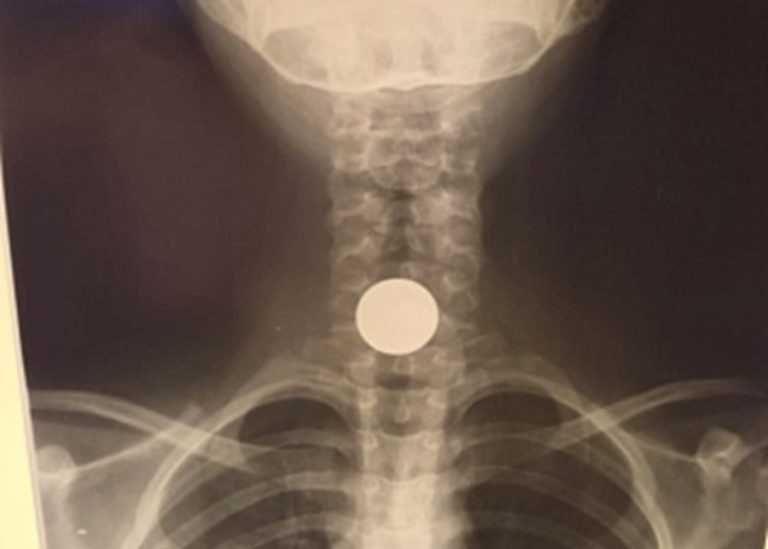

Девятилетняя пациентка поступила в стационар после необычного происшествия во дворе. Играя с друзьями, ребенок решила спрятать пятикопеечную монету под языком, но случайно проглотила ее.

Медики оперативно извлекли инородный предмет из пищевода под общим наркозом. Как пояснили врачи, девочка вовремя обратилась за помощью — монета застряла у входа в пищевод, что могло привести к серьезным последствиям.

Фото: Балаковская городская клиническая больница.